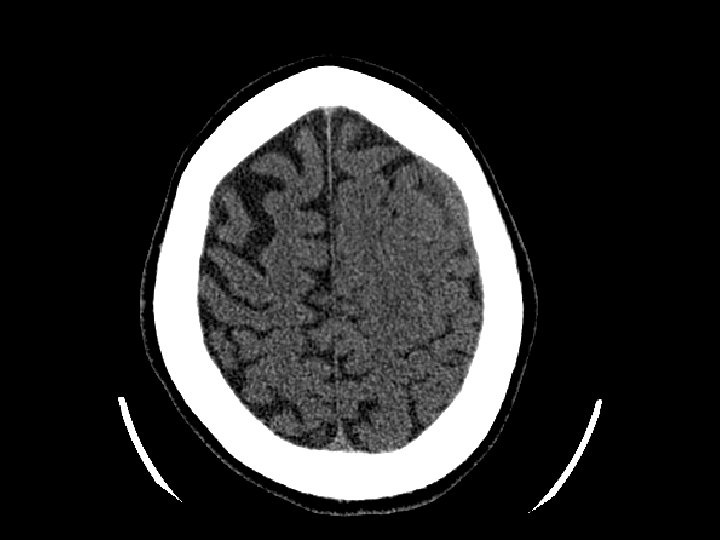

Tụ máu dưới màng cứng • Chảy máu giữa màng cứng và não – Thường gặp hơn tụ máu ngoài màng cứng – 30% bệnh nhân CTSN có tụ máu dưới màng cứng • CT: khoảng tụ máu hình liềm • Có thể gặp cấp tính, bán cấp hoặc mãn tính – Bán cấp hoặc mãn tính diễn biến nhiều ngày/tuần sau chấn thương

Tụ máu dưới màng cứng • Tăng nguy cơ ở người già (cơ chế chấn thương không nghiêm trọng) – Não teo nhỏ đi theo lứa tuổi gây giãn các tĩnh mạch cầu nối ở khoảng dưới màng cứng • Có thể tăng dần kích thước (chậm hơn máu tụ ngoài màng cứng) • Phẫu thuật dẫn lưu nếu tổn thương gây choán chỗ và đè đẩy